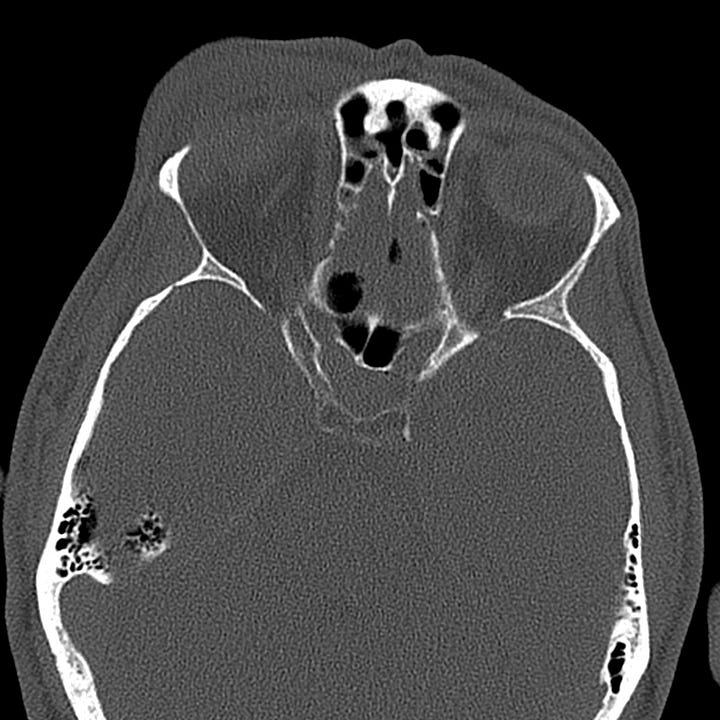

Tension pneumocephalus due to temporal bone fracture. Bifrontal subdural air collections with mild compression of the frontal parenchyma. Opacified left mastoid air cells are consistent with an acute tem- poral bone fracture. Air in the cisterns and left sylvian fissure indicate arachnoid injury.